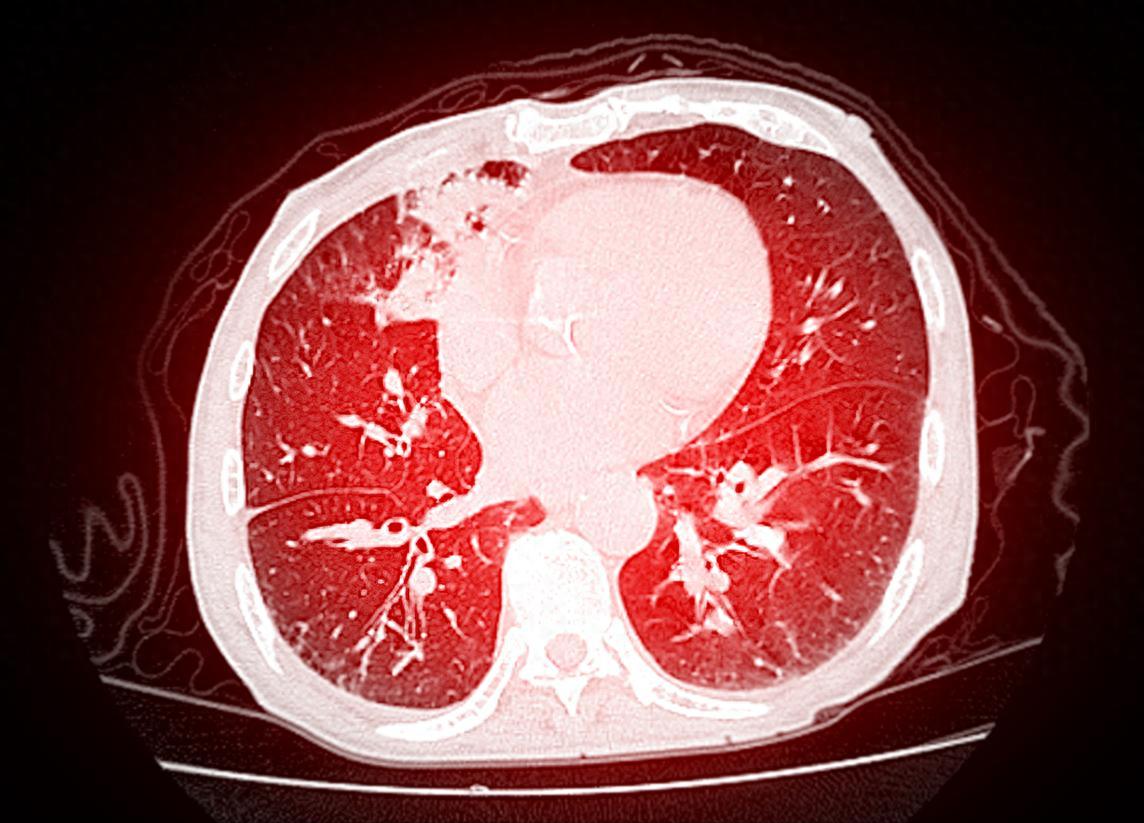

Understanding Your Lung CT Report! Don't Panic When Seeing These Terms

Does receiving a lung CT report full of dense medical terminology make you nervous? Actually, many indicators turn out to be "false alarms"! Master these 11 common descriptions to easily assess your lung health status: